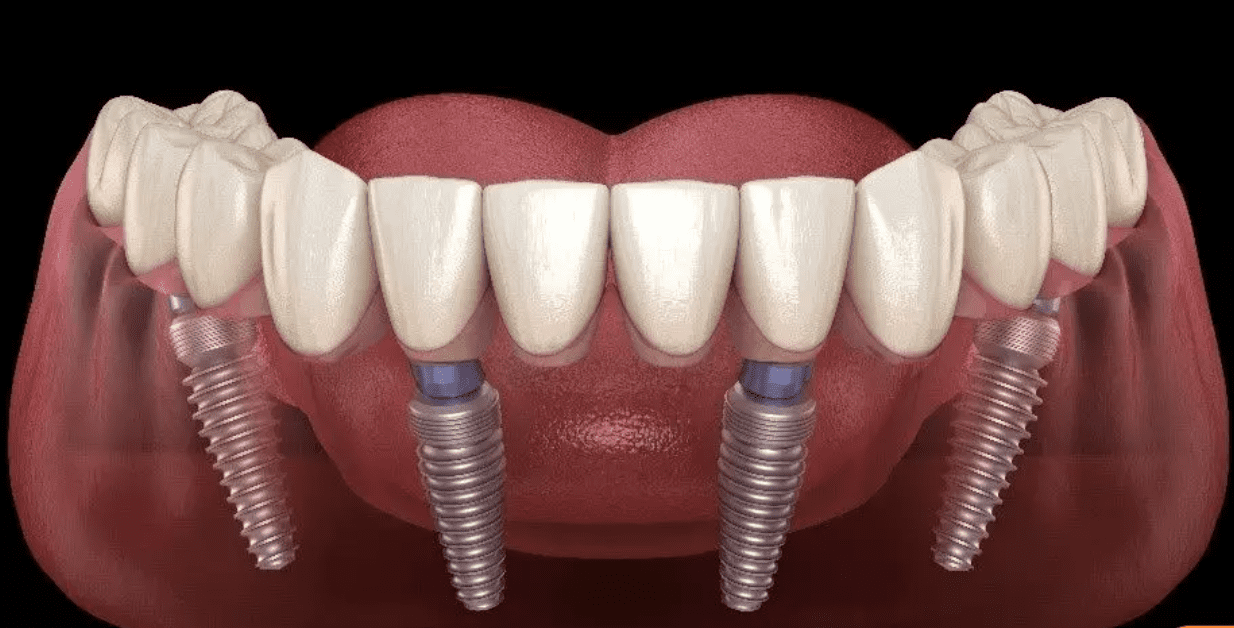

A dental implant surgery is structured in such a particular manner that it fixes perfectly in the jaw of the patient and makes them feel comfortable in the best possible manner. A dental implant consists of the following parts which are confined togetherly to form this perfectly useful component.

CROWN

A crown is nothing but a tooth-shaped cap that is placed over an existing tooth to make the existing one even more strong. It is capable of repairing a fractured tooth. A dental implant is a surgical implant that replaces a missing tooth and is topped with a crown to make it seem and function like a natural tooth. A crown is merely a replacement for the visible top section of the tooth, rather than a root replacement alternative. A crown is also known as a “cap” because it works as a cap to cover the tooth. Crowns are held in position by being attached to the remaining teeth surrounding the gap, which frequently means that a minuscule space remains.

ABUTMENT

The abutment is a little piece of metal that connects the implant post to the prosthetic. One side is intended to screw into the inside of the implant post, while the other is intended to hold a dental prosthetic. Depending on the type of prosthetic that needs to be supported, numerous types of abutments may be employed. A dental crown, for example, may resemble a stumpy screw, whereas an abutment used for an implant-supported denture may have unique attachments that clip into the denture. Some abutments can also be angled to ensure a natural appearance once the prosthetic is installed.

SCREW

The dental implant surgery procedure employs miniature screw-shaped prostheses to secure artificial teeth for both dental restorations and individual tooth replacement. The dental screw is the device that secures the abutment to the implant. This fastener is threaded and is normally tightened until it reaches its ultimate seating position. There are mechanical and electrical torque measurement devices available that will indicate the magnitude of the torque applied to the screw.

FIXTURE

The fixture, also known as an implant post, is a tiny, cylindrical screw that is inserted into the jawbone to serve as an artificial tooth root. Because the fixture is intended to simulate the function of genuine tooth roots, it is tapered at the base, just like a normal tooth root. Because of its biocompatibility, titanium is often used to make implant posts. In certain situations, they are additionally covered with hydroxyapatite, which aids in the integration of the implant post with the surrounding bone. Dental implants are the only option for replacing lost teeth that have a component that works like natural tooth roots. After inserting the implant post into the jawbone, it will fuse with the surrounding bone in a process known as osseointegration. Oncethe implant post has bonded, it will behave almost identically like a natural tooth root, providing for natural chewing function and look.